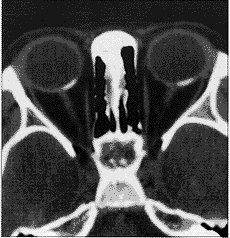

图4 双眼计算机断层扫描

脉络膜骨瘤是脉络膜的一种良性骨性肿瘤,典型地见于10多岁至20多岁健康年轻女性。约25%的患者中,这种异常为双侧性1,2。此肿瘤一般发展并不快2~4。计算机断层扫描检查及A超和B超检查显示该肿瘤是一典型的脉络膜骨瘤。但是,此肿瘤的迅速增大是个例外。该肿瘤是在检查斜视时意外地被发现;与其它报告相比,这些早期肿瘤很小,而且患者很年轻。据我们所知,这是所报告的有此情况的最年轻患者。我们认为发生在小年龄的骨瘤可迅速增大。